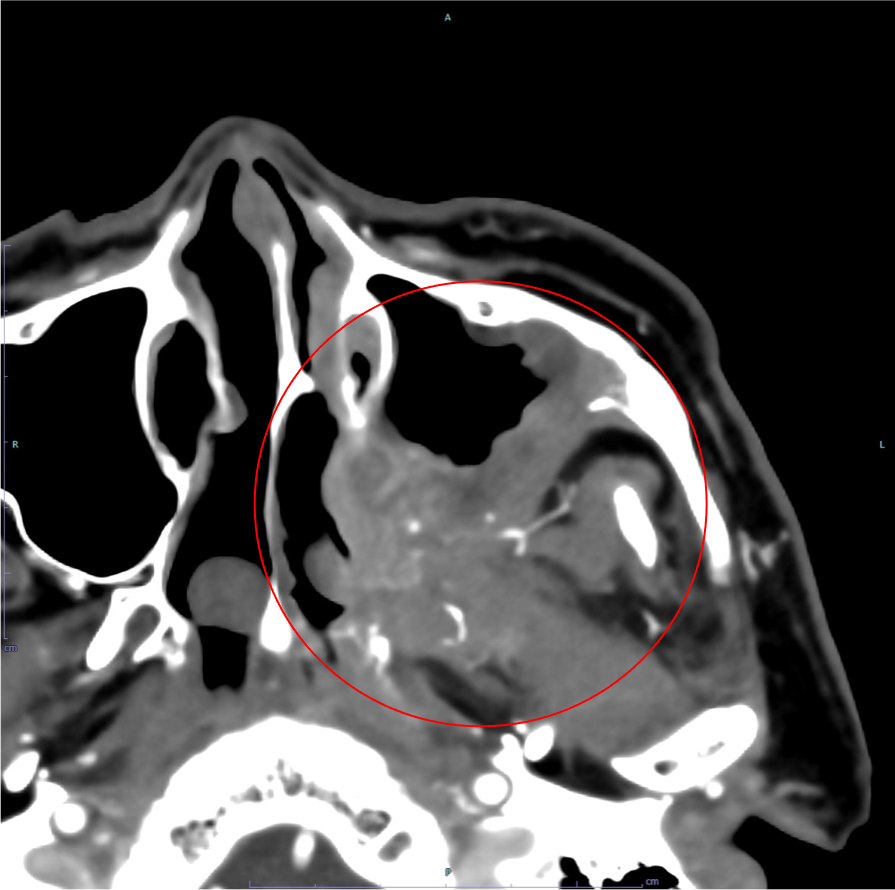

左頬部腫脹を自覚し前医受診し、撮像されたCTで上顎洞癌が疑われたため、当院耳鼻咽頭科を紹介受診された。受診時には左上顎部の感覚低下や軽度の開口障害も見られており、各種検査の結果、最終的に上顎洞癌cT4bN0M0の診断でRADPLATの方針となった。

平衡相では腫瘍の大きさや広がり、周囲組織との関係の評価、リンパ節転移の評価を行う。